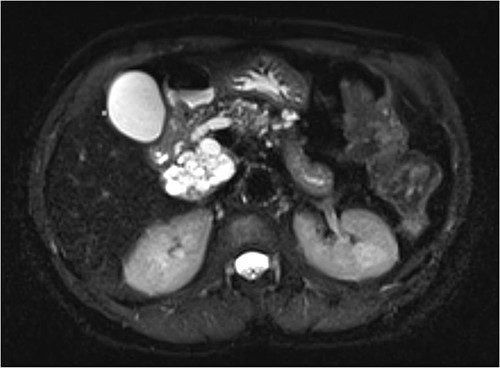

Interval MRI after 1 year showed an increased size of 8 cm with associated main pancreatic duct dilation up to 8 mm, which was not previously present (Fig. 2). Repeat EUS and biopsy demonstrated atypical cytology. The presence of atypical cytology and progressive duct dilation suggested the possibility of a malignant process and surgical resection was recommended.

Increased diameter of lesion and dilation of main pancreatic duct on interval MRI.